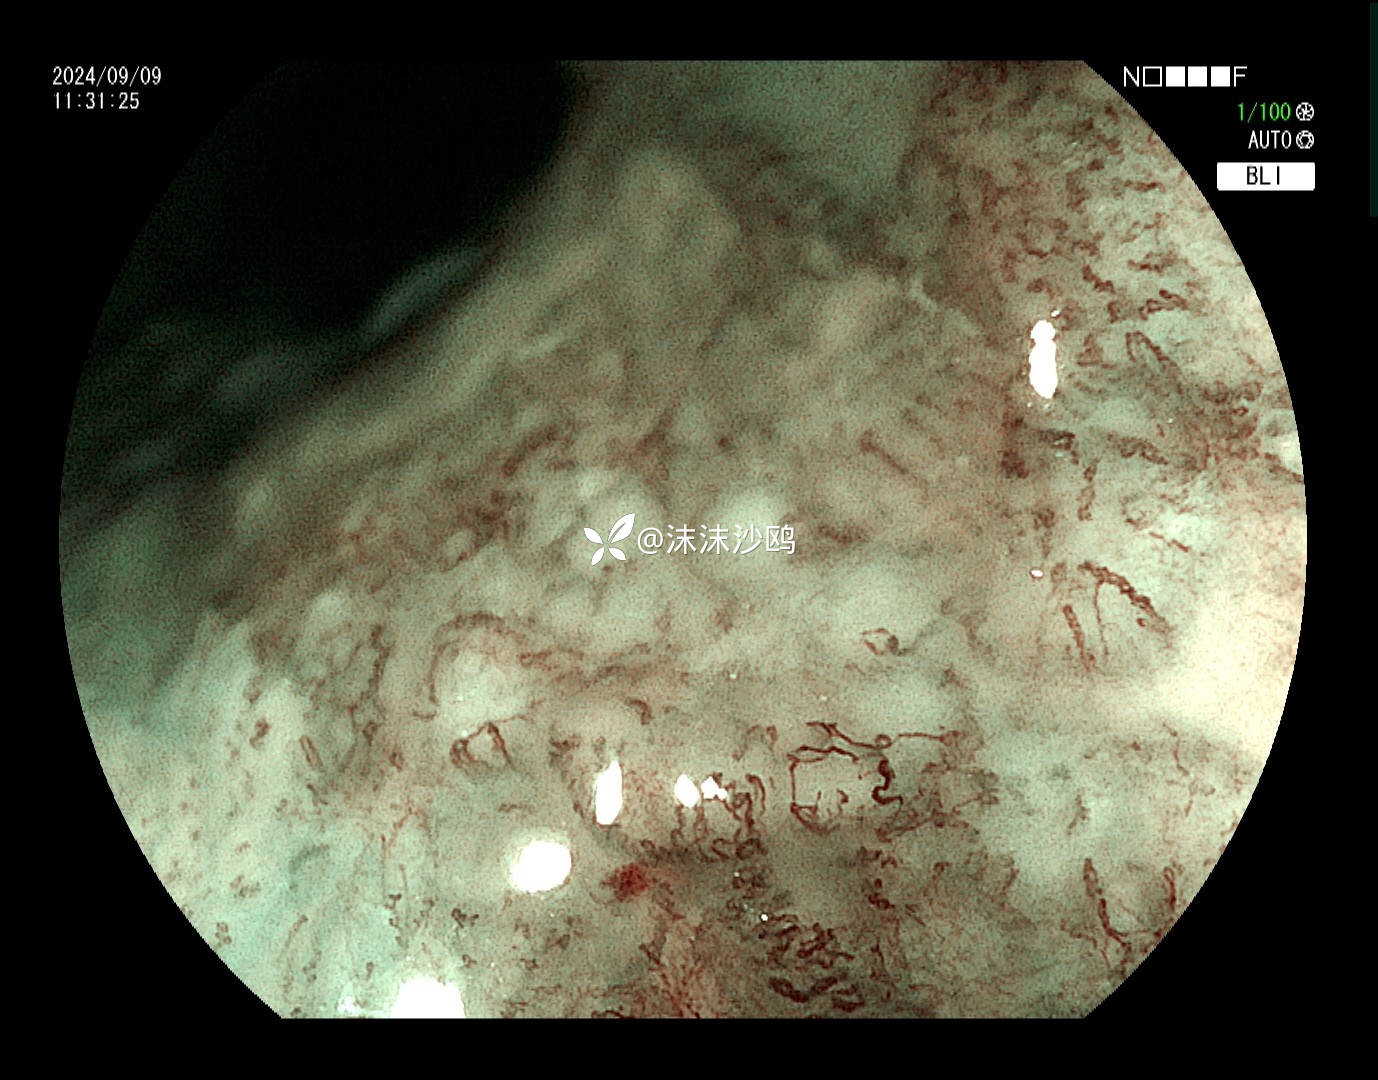

ME

病灶肛侧

该患者平素无明显症状,吸气注气观察病灶延展性,柔软度可,白光观察粘膜呈现发红粗糙,BLI放大观察呈现明显茶褐色,可见B1型血管,局灶可见紊乱生长的B2型血管,并见AVA区域,感觉小于0.5mm。镜下考虑浸润深度,不超过SM1,应该有内镜下D的可能性。等病理结果,希望符合内镜诊断。